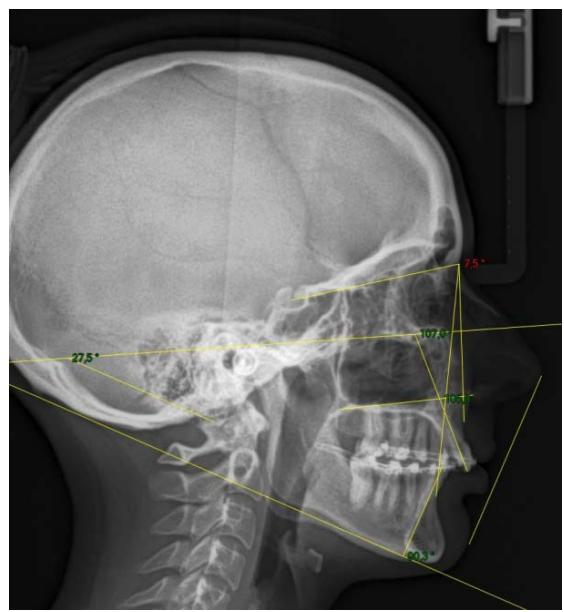

La comparaison des télé radiographies permet d'objectiver le redressement incisif mandibulaire et la distalisation molaire mandibulaire obtenue. Nous observons également le maintain des axes incisifs au niveau de l'arcade maxillaire.

On note un redressement incisif très important. En effet, l'axe incisif mandibulaire est passé de $112^{\circ}$ à $90.3^{\circ}$ en 6 mois. Une distalisation molaire de 3 MMA également été obtenu. Les axes incisifs maxillaires ont été maintainus, ce qui correspond parfaitement à notre objectif de départ.

Télé radiographies de profil: comparaison entre l'image de début de traitement et l'image de contrôle après 6 mois de traction sur l'ancrage par fil dans la branche montante mandibulaire. L'angle incisif est passé de 112 à $90,3^{\circ}$.